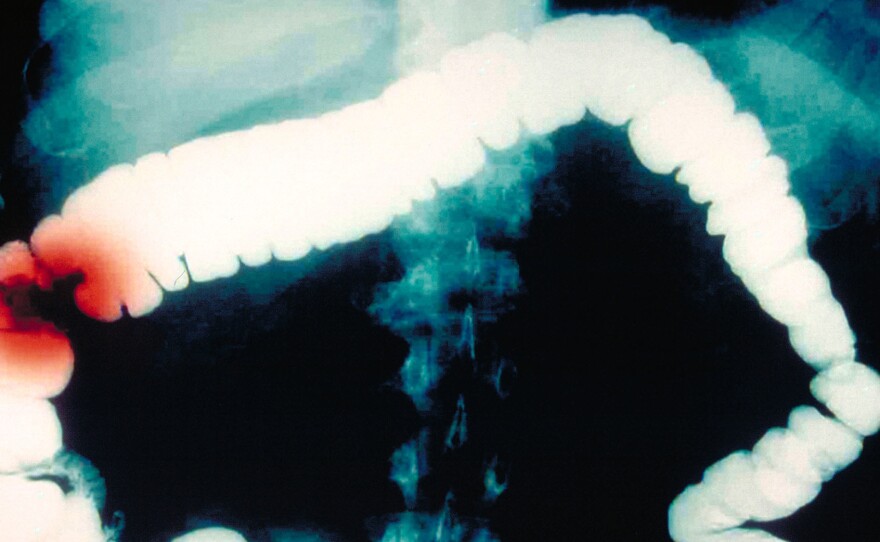

Another possibility is that, once people turn 50, they will follow the current medical guidance and get colonoscopies or other recommended screening tests, which can actually prevent colorectal cancer by finding and removing precancerous polyps. And their risk profile could end up looking much like it does today.

On one point there is broad agreement among doctors and researchers treating and studying this disease: The increased screening for colorectal cancer, which can involve removing polyps before they become cancer, has been a significant factor in reducing the burden of this illness.